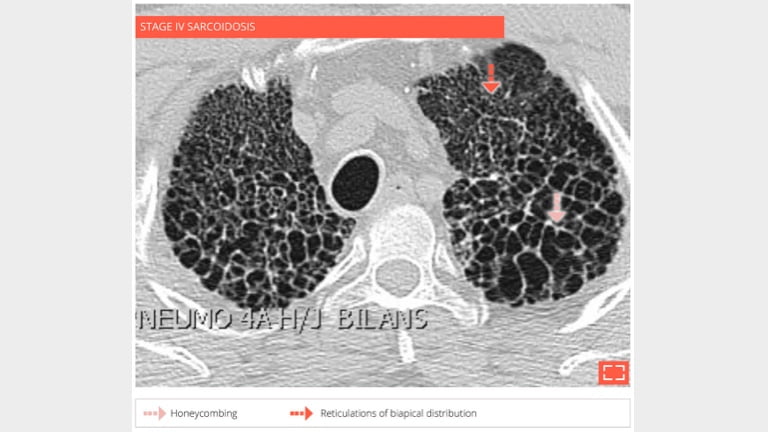

56-year-old man with history of sarcoidosis. Typical honeycombing in a upper lobe distribution.

5. Honeycombing

Honeycombing

• Coronal reformation in the same patient shows the association of honeycombing and reticulation in lung apices.

• Distribution of fibrosis to apices makes this fibrosis incompatible with UIP.